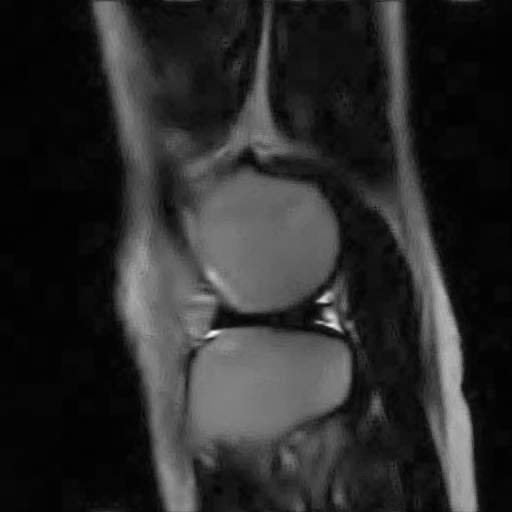

V-C Denoising of a magnitude MR knee image

We have also applied our CURE-LET denoising algorithms to an actual magnitude MR image of the knee. This 16-bit raw image has been acquired on a Siemens 1.5 Tesla Magnetom Sonata MR system, following a sagittal T2-weighted protocol. The standard deviation of the complex Gaussian noise has been estimated from a signal-free region of the squared data, as , and subsequently treated as known.

Fig. 11 shows the denoising results of the various CURE-LET algorithms. As observed, the noise is efficiently attenuated and the contrast is significantly improved, owing to a proper reduction of the signal-dependent bias introduced by the noise.